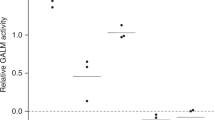

The GALT enzyme level of the eight patients was within the expected range for patients with classic galactosemia, using the spectrophotometric method, <6 μmol/h/gHb (Table 1). Interestingly, the most frequent mutation in Caucasian populations, p.Gln188Arg, was not found in any of the Cypriot patients with classic galactosemia. Two patients (siblings) were found to be homozygous for the p.Lys285Asn mutation and their parents were confirmed to carry the same mutation, while another three patients appeared to be homozygous for the p.Lys285Asn mutation but only one of their parents carried this mutation. For three patients, none of the 11 exons could be amplified. All the above findings could be explained by the presence of a large deletion covering the whole gene. Patient samples in which GALT exons could not be amplified were analyzed for the presence of the previously reported 5.5 kb GALT deletion characterized by an intervening complex junction fragment (Coffee et al. 2006). All patients were apparently negative for the 5.5 kb deletion (Fig. 1) suggesting the existence of a novel large GALT deletion.

The level of GALT activity in patients homozygous for the new deletion would be expected to be zero since the deletion abolishes the whole of the gene. This was found to be so in two of our patients (0 and 0.05 μmol/h/g Hb), but the third patient had a residual activity of 5.9 μmol/h/g Hb (Table 1). This is probably due to the limitations of the spectrophotometric method we used to measure GALT. Use of a more specific and sensitive method like LC-MS/MS (Li et al. 2010) would probably reveal undetectable activity.